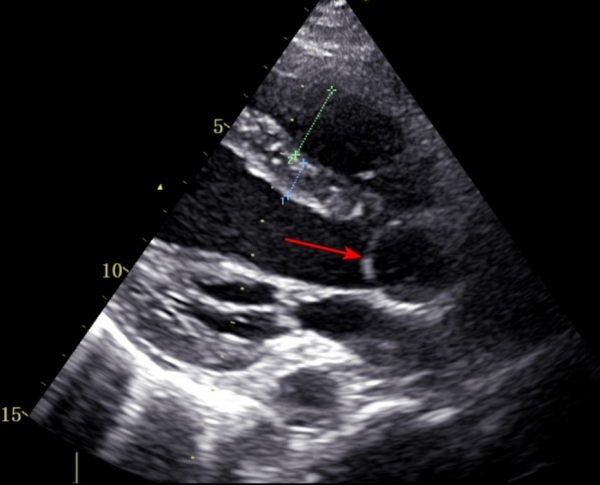

术前心脏超声:主动脉右冠窦菲薄,呈囊带样向右房膨出,随血流呈风袋样飘动,瘤壁可见破口约10mm。